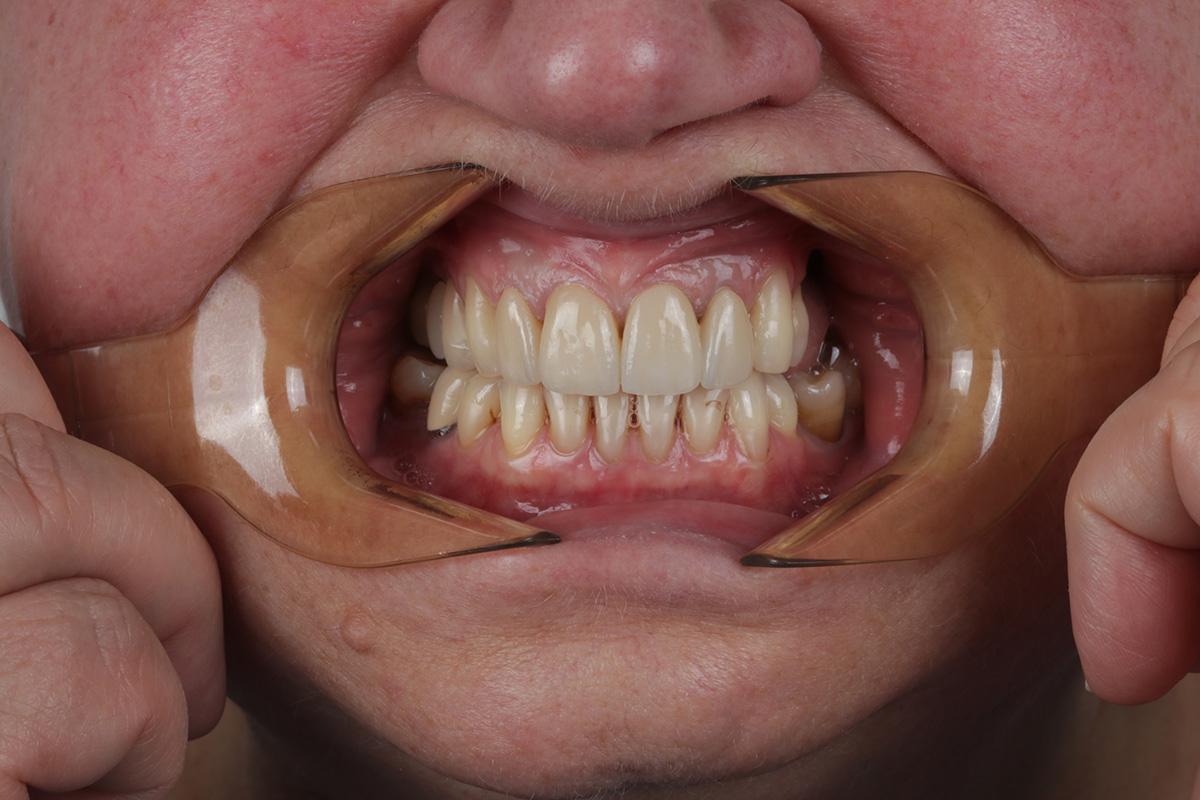

Przedstawiamy metamorfozę naszej Pacjentki, której bardzo zależało na wyprowadzeniu swoich problemów zarówno leczniczo jak i estetycznie.

Pierwszy etap to kompleksowa konsultacja u dr Joanny Zawirskiej-Poły. Podczas tej wizyty zostało wykonane badanie przedmiotowe, podmiotowe, badanie mięśni i stawów, analiza okluzji, badanie stomatologiczne, tomografia komputerowa, rejestracja fotograficzna i długa rozmowa z Pacjentką na temat jej oczekiwań.

Pacjentka, zgłaszając się już na kolejną wizytę świadomie podjęła opcję pośrednią z proponowanych działań: wyleczenie zębów zachowawczo, endodontycznie z zabezpieczeniem protetycznym, estetyczne korekty uśmiechu licówkami, ćwierćkoronami i koronami, jednak bez pełnej przebudowy zwarcia (z zachowaniem starszych odbudów w strefach bocznych, które były wykonane na implantach w przeszłości), która jest zawsze najbardziej polecana, odtwarza prawidłowe kontakty, a także umożliwia lekarzowi i technikowi najlepsze warunki do nadania odpowiednich i harmonijnych kształtów. Te wszystkie działania chronią na przyszłość staw skroniowo-żuchwowy.

Następnie dr Joanna przekierowała Pacjentkę na kompleksowe działania endodontyczne do dr Aleksy Muchy.Po tym dr Joanna mogła przystąpić do działań protetycznych.

Prace protetyczne odbywały się we współpracy z Laboratorium Dental Scan, ściślej z Panią Anną Simierską i Agatą Łatyk-Banasik.

Cała terapia, jak zawsze w takich przebudowach, nawet częściowych wiąże się z bezwzględnym zwieńczeniem wykonania szyny ochronnej, której konstrukcja jest zawsze uwarunkowana indywidualnie. Zalecenia jej noszenia przez lekarza również są indywidualne i mogą się zmieniać w perspektywie czasu.

Tak wyprowadzony Pacjent powinien stawiać się (oczywiście zawsze z szyną) na wizytach kontrolnych co 6 m-cy. W międzyczasie z zaleceń lekarza z pewnością wskazane mogą być zabiegi higienizacyjne u naszych Pań higienistek, by podtrzymać u Pacjenta zdrowy stan przyzębia.